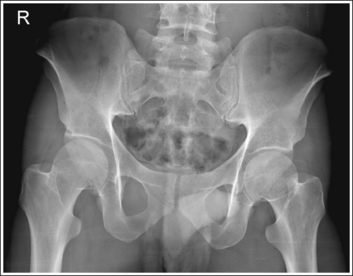

The pelvis demonstrates an AP projection. The ischial spine is aligned with the pelvic brim, the sacrum and coccyx are aligned with the symphysis pubis, and the obturator foramen is open.

• Detecting pelvis rotation. Rotation on an AP hip projection is initially detected by evaluating the relationship of the ischial spine and the pelvic brim, the alignment of the sacrum and coccyx with the symphysis pubis, and the degree of obturator foramen demonstration. If the patient was rotated toward the affected hip, the ischial spine is demonstrated without pelvic brim superimposition, the sacrum and coccyx are not aligned with the symphysis pubis but are rotated away from the affected hip, and the obturator foramen is narrowed (see Image 1). If the patient has been rotated away from the affected hip, the ischial spine is not aligned with the pelvic brim but is demonstrated closer to the acetabulum, the sacrum and coccyx are not aligned with the symphysis pubis, but are rotated toward the affected hip, and the obturator foramen is widened (see Image 2).

IMAGE 1

IMAGE 2

The ischial spine is demonstrated without pelvic brim superimposition, the sacrum and coccyx are not aligned with the symphysis pubis but are rotated away from the affected hip, and the obturator foramen is narrowed. The patient was rotated toward the affected hip. The femoral neck is foreshortened, and the lesser trochanter is demonstrated in profile. The patient's leg was externally rotated.

Rotate the patient away from the affected hip until the ASISs are positioned at equal distances from the imaging table. Internally rotate the patient's leg until the foot is angled 15 to 20 degrees from vertical and the femoral epicondyles are positioned parallel with the imaging table, as shown in Figure 7-4.

The ischial spine is not aligned with the pelvic brim but is demonstrated closer to the acetabulum, the sacrum and coccyx are not aligned with the symphysis pubis but are rotated toward the affected hip, and the obturator foramen is clearly demonstrated. The patient was rotated away from the affected hip (left posterior oblique [LPO] position).

Rotate the patient toward the affected hip until the ASISs are positioned at equal distances from the imaging table.